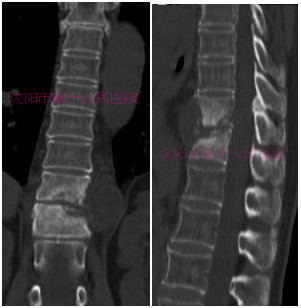

术前CT显示:胸11-12椎体骨质破坏,椎间死骨形成,病椎硬化,椎旁软组织肿胀。

术前增强MRI提示:胸11-12椎体T1加权高信号,椎间混杂信号,椎旁可见囊性结构,内部为低信号,边缘可见强化,椎旁脓肿可能性大,椎体感染可能性大。

术前三维CT提示:胸10-11椎体骨质破坏严重,可见死骨形成,椎体后壁缺损,椎管显露,椎旁软组织肿胀。